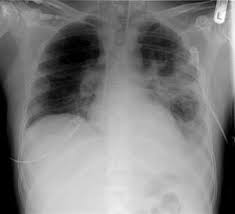

Die Lungenentzundung Ist Eine Schwere Erkrankung Die Nicht Einfach Zu Diagnostizieren Ist Gesundheit